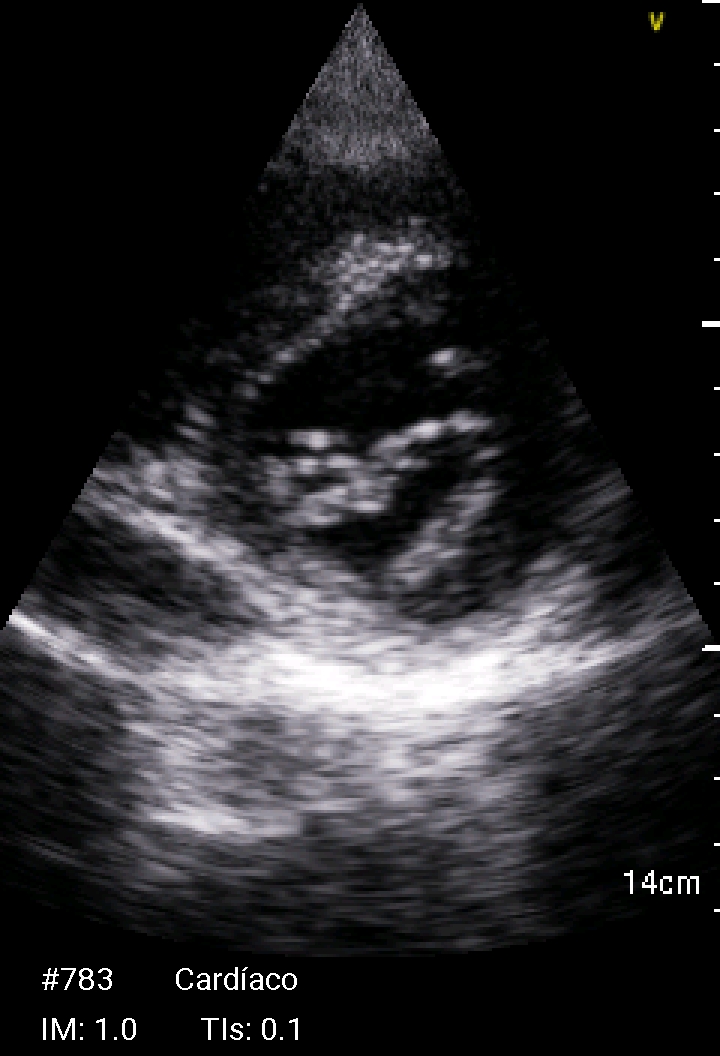

Ante la presencia de fiebre y soplo cardiaco se realiza ecocardioscopia.

Ecocardioscopia: Válvula mitral con engrosamiento de ambas valvas e imagen nodular no móvil en cara auricular del velo anterior (cambios degenerativos versus vegetación). Ventrículo izquierdo no dilatado ni hipertrófico, FEVI preservada. Ventrículo derecho normal. Mínimo despegamiento de hojas pericárdicas en cara posterior.